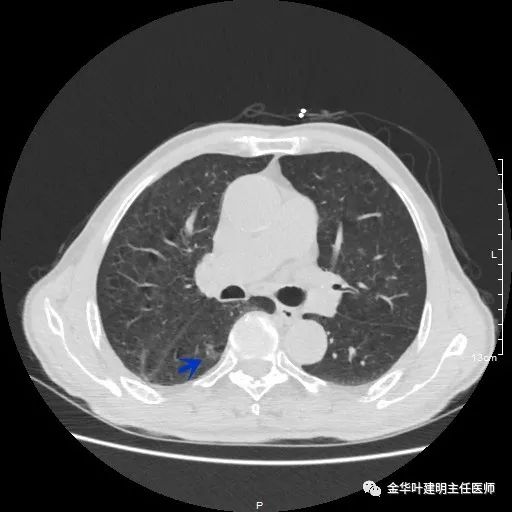

以上示右下叶病灶6。同样是囊腔型病灶,但较前几个范围小,可囊壁同样为磨玻璃影,也是较为典型的囊腔型肺癌表现,单灶来看可下叶背段切除。

如此多的病灶,这样的年纪该如何考虑?我们先来分一下:病灶3与病灶5是混合磨玻璃及实性病灶,不能继续观察等待,得干预;病灶1、病灶4与病灶6是囊腔型肺癌考虑,恶性程度低,可观察随访,若处理病灶3与5的话,能附带则要附带处理;病灶2在左侧,目前较小,而且在肺外周部位,若对右侧进行干预,则左侧先观察随访,下次可考虑局部楔形切除。